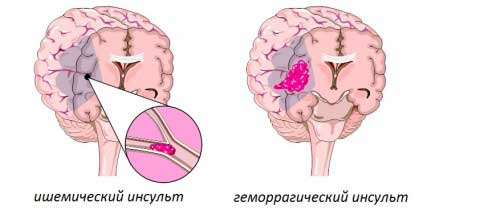

Согласно медицинской классификации, цереброваскулярные заболевания делятся на две основные категории: острые и хронические. В первую группу входят:

- ишемическая атака;

- гипертоническая энцефалопатия;

- ишемический инсульт, неуточненный геморрагический инсульт.

Хроническая форма заболевания проявляется дисциркуляторной энцефалопатией, которая делится на несколько типов:

- эмболия, при которой сосуды блокируются сгустками, образующимися в крупных артериях и перемещающимися в более мелкие с током крови;

- кровоизлияние, возникающее в результате разрыва сосуда, что может привести к геморрагическому инсульту;

- тромбоз, при котором бляшки закупоривают просвет сосуда, вызывая его сужение.

| Ишемический инсульт | Возникает из-за блокировки кровотока в мозге, обычно из-за тромба. | Слабость или паралич в лице, руке или ноге (особенно с одной стороны тела), спутанность сознания, трудности с речью или пониманием, головная боль, головокружение, потеря координации. |

| Геморрагический инсульт | Происходит из-за разрыва кровеносного сосуда в мозге, приводящего к кровоизлиянию. | Сильная головная боль, внезапная потеря сознания, тошнота и рвота, жесткость шеи, судороги. |